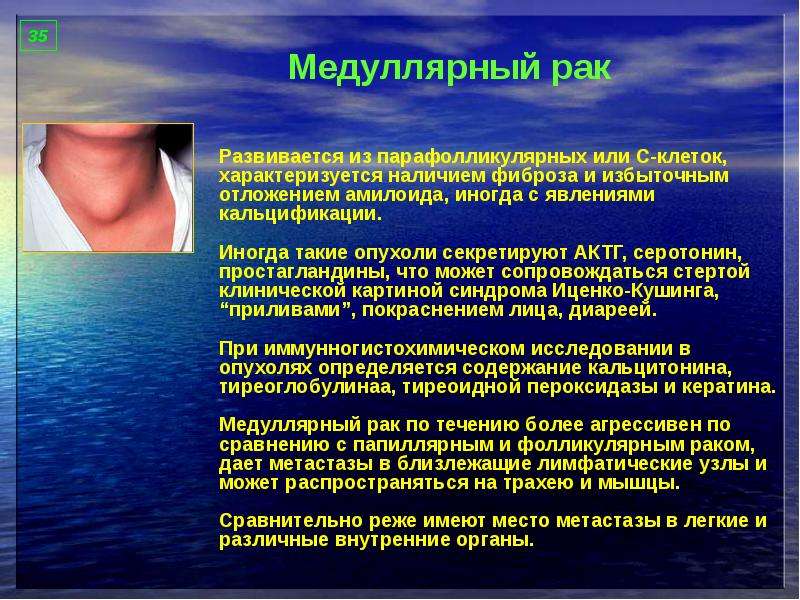

Фотографии опухоли медуллярной аденокарциномы

Раздел: Снимки-откровения